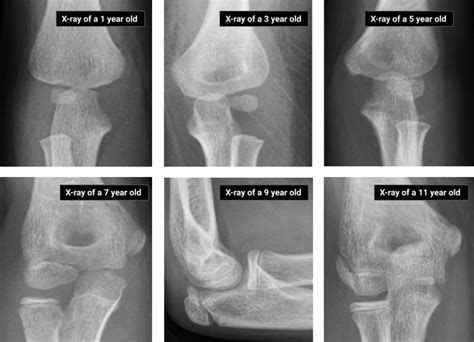

Nursemaid elbow, also known as radial head subluxation, is a common injury in young children, typically occurring between the ages of 1 and 4. This condition happens when the radius bone in the forearm slips out of its normal position at the elbow joint. Understanding the causes, symptoms, diagnosis, and treatment of nursemaid elbow is crucial for parents and caregivers to ensure prompt and appropriate care.

Diagnosing nursemaid elbow typically involves a physical examination by a healthcare provider. The provider will assess the child's arm and elbow for signs of injury and may perform a gentle manipulation to confirm the diagnosis. In some cases, a Nursemaid Elbow Xray may be ordered to rule out other potential injuries, such as fractures or dislocations. However, X-rays are not always necessary for diagnosing nursemaid elbow, as the injury does not typically show up on imaging studies.